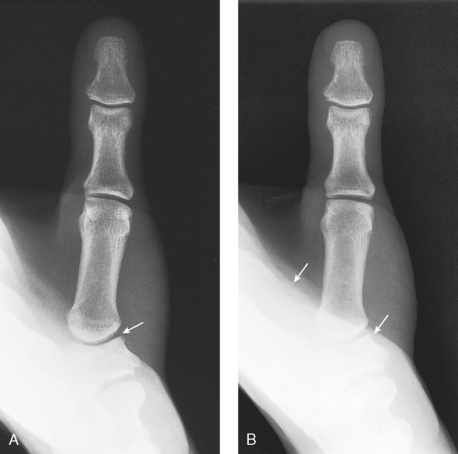

Position of part: When radiographing individual digits (except the first), take the following steps:

• Place the extended digit with the palmar surface down on the unmasked portion of the IR.

• Separate the digits slightly, and center the digit under examination to the midline portion of the IR.

• Center the PIP joint to the IR (Figs. 4-13 to 4-15).

Structures shown: A PA projection of the appropriate digit is visualized (Figs. 4-16 through 4-19).